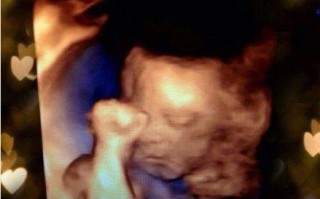

备孕期间照B超安全吗?对胎儿发育有影响吗?

当然可以!备孕期间不仅可以照B超,而且在很多情况下,医生会建议进行B超检查,这其实是备孕前一个非常重要的环节,通常被称为“孕前检查”或“备孕评估”的一部分,B超检查可以帮助医生和您更全面地了解身体状况...